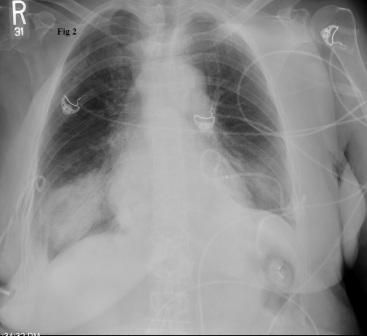

A young woman experienced acute onset of high fever, productive cough, and right-sided pleuritic pain. She was not in sickle cell crisis. Do the images here shed light on cause of symptoms?

Results of a physical examination and CT scan of the chest offer clues to this patient's diagnosis.